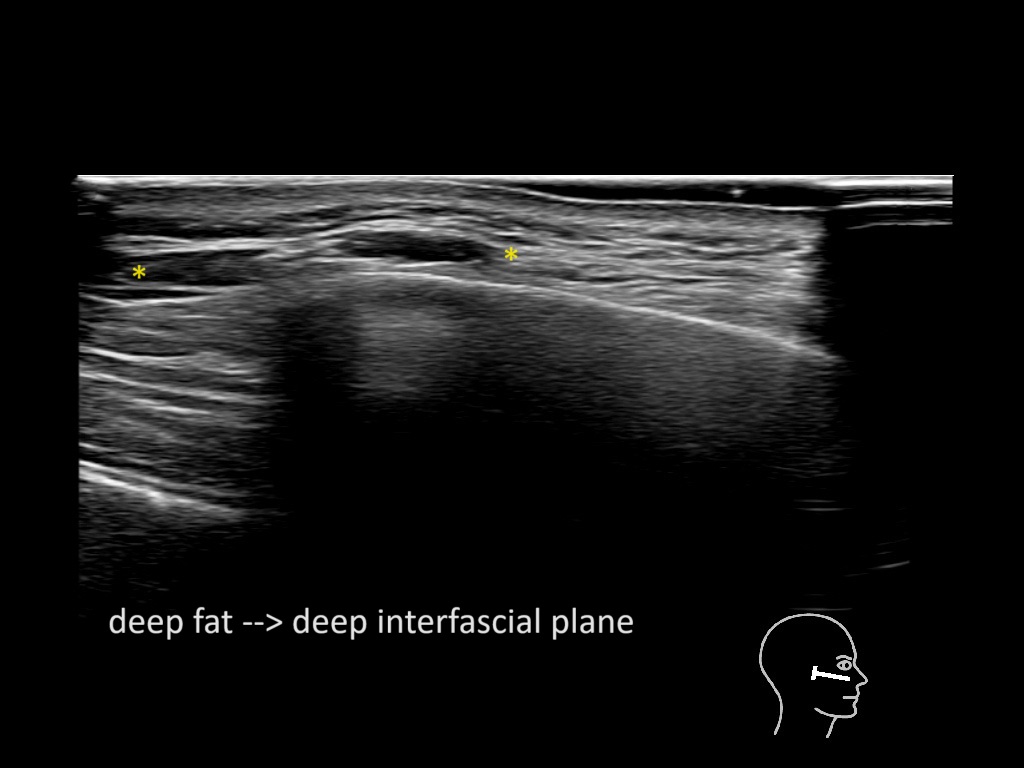

Filler behavior - Temple zygoma US

Study the first image to recognize the different layers. If you are sure about the layers, swipe to the second image to view the answer (if applicable).